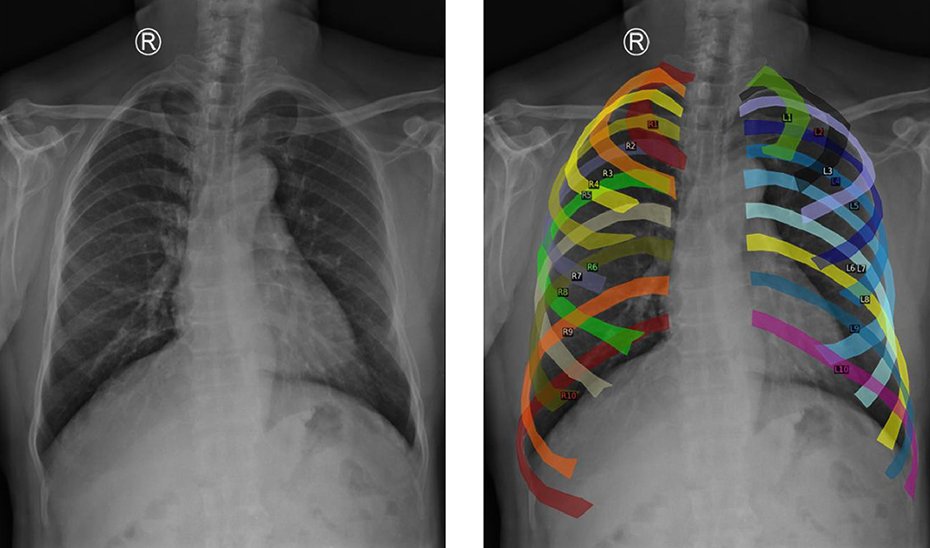

En el artículo ‘Localization and classification of abnormalities on chest X-ray images using a Mamba-YOLOvX model’, publicado en la revista Expert Systems with Applications, se presenta el nuevo modelo Mamba-YOLOvX. Este modelo, basado en algoritmos de aprendizaje automático y redes neuronales convolucionales, permite localizar lesiones de diferentes tamaños de manera rápida y efectiva.

El nuevo modelo combina la información global de la imagen, como la forma de los pulmones o la posición del corazón, con la información local, los pequeños detalles que pueden indicar lesiones o irregularidades. Además, incorpora mecanismos de atención espacial y de canal que se enfocan en las zonas relevantes de la radiografía, ignorando lo que no aporta información, lo que permite detectar problemas a diferentes escalas.